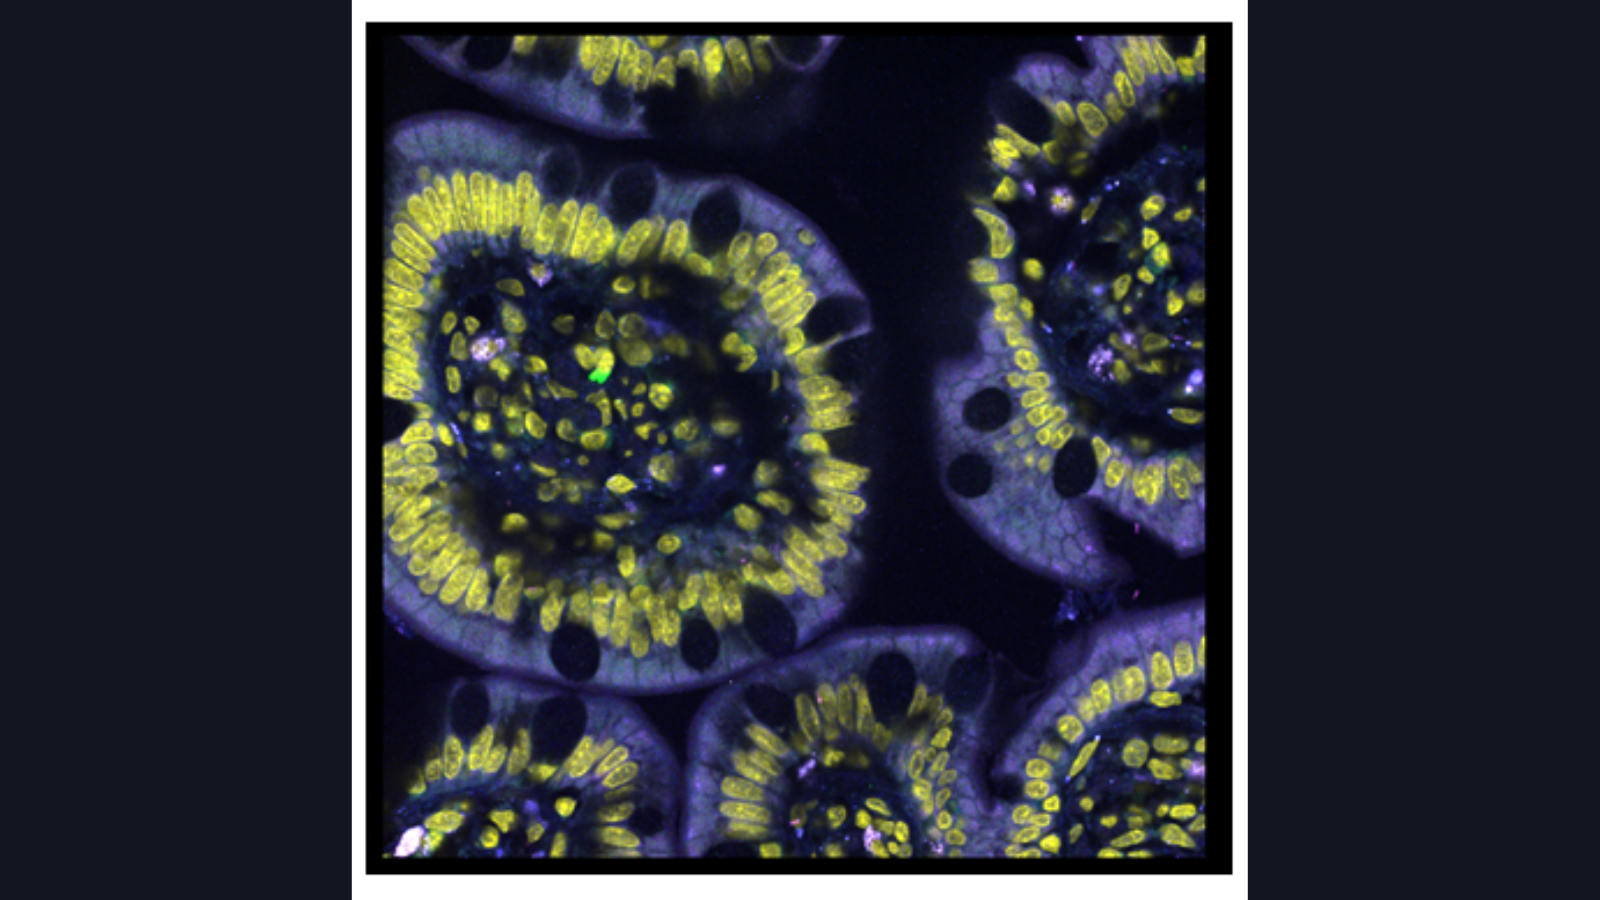

Human colon cells made by the researchers at Stanford University's Bendall lab that uses single-cell metabolic regulome profiling (scMEP).

CODEX of healthy colon, courtesy of John Hickey at Stanford

RNA transcripts in sections of the small intestine, courtesy of Dr. Long Cai at Cal Tech